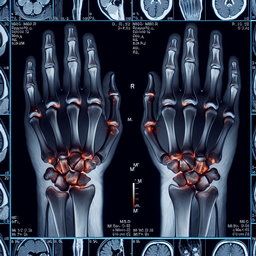

МРТ променезап'ясткового суглобу

МРТ променезап'ясткового суглобу — це діагностична процедура, яка дозволяє отримати детальні зображення кісток, суглобів, зв'язок, сухожиль та м'яких тканин у цій ділянці. Цей метод є неінвазивним і не використовує іонізуюче випромінювання.